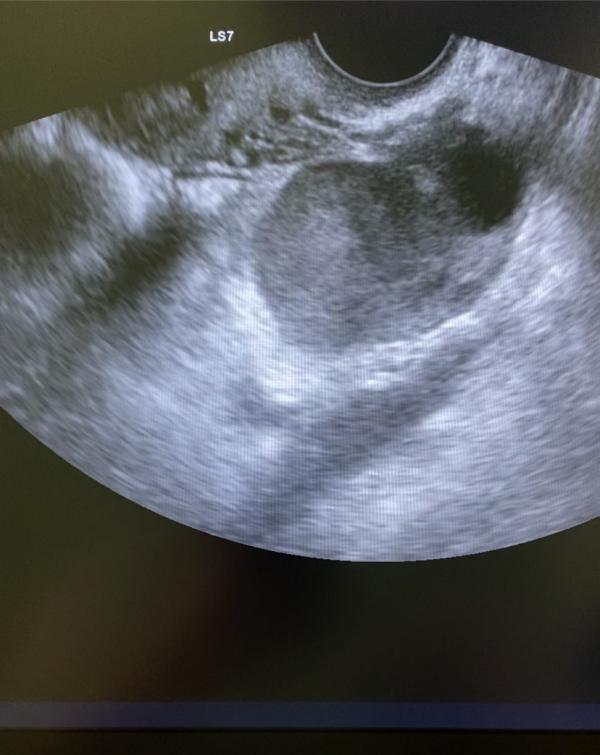

Этим постом хочу предостеречь женщин от самостоятельного прерывания беременности.

Основной довод женщины , что она всегда так делает и было всё хорошо 😭 ( 8 абортов)